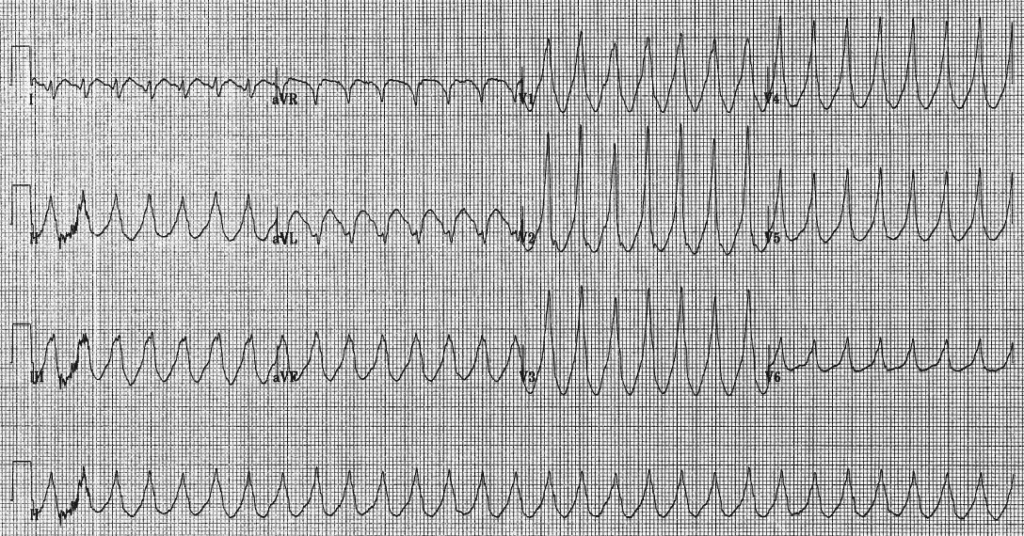

Основным и наиболее информативным исследованием является электрокардиография, или ЭКГ, а также электрокардиограмма по Холтеру (запись проводится непрерывно 24–72 часа, в состоянии покоя и при нагрузках).

ЭКГ-признаки синусовой тахикардии представлены на этой иллюстрации:

Показатели при регистрации электрокардиограммы во время желудочковой и наджелудочковой тахикардии отличаются. Желудочковая форма представлена расширенными комплексами QRS. Синусовая тахикардия у детей на ЭКГ имеет ускоренный ритм, при котором количество сокращений доходит до 200 ударов в минуту. Желудочковое нарушение ритма представляет серьезную опасность для жизни малыша.

Другая синусовая тахикардия у детей на ЭКГ выглядит в виде правильных и регулярных сердцебиений. Ритм правильный, количество сокращений обычно не превышает 140 в минуту. Наджелудочковая тахикардия быстро появляется и исчезает, что часто не ощущается ребенком и видно только на кардиограмме. Зубцы Р имеют различный вид, а комплексы QRS остаются неизмененными. Интервалы R-R между сокращениями сердца укорочены.